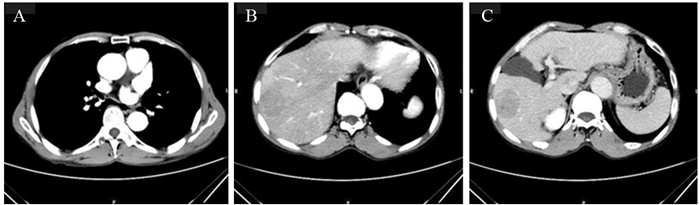

1 病例资料患者,男,63岁。2018年8月,因“上腹部疼痛4月,加重伴剑突下疼痛12 h以上”入院。家属诉患者入院前4月因右上腹疼痛,于当地医院检查,诊断“肝癌肝内转移”,并给予“阿帕替尼片、恩替卡韦片、肝苏颗粒、甘草酸二铵肠溶胶囊”口服。定期复查增强CT。1周前,因右上腹胀痛于门诊就诊,腹部增强CT示肿瘤稳定,见图 1。给予盐酸曲马多缓释胶囊100 mg每12 h口服一粒,疼痛控制可。12 h前,无明显诱因下出现剑突下疼痛,呈持续性撕裂样疼痛,先后口服2粒盐酸曲马多缓释胶囊不缓解,伴有头晕,无声嘶、胸痛、胸闷,无恶心、呕吐,无血尿等。否认高血压、冠心病、先天性心脏病、胸部外伤、梅毒等病史。查体:体温36.6℃,脉搏71次/分,呼吸20次/分,血压:169/110 mmHg。神志清楚,急性痛苦面容。言清语利,无口角歪斜、复视、视力减退等,四肢肌力感觉正常,颈部未闻及血管杂音,心肺(-)。无声嘶、声哑; 上腹部疼痛,剑突下压痛,未触及异常搏动性肿块; 肝脾肋下未触及,肠鸣音4次/分; 左上腹可闻及血管杂音,余中下腹部未闻及血管杂音。双上肢桡动脉、足背动脉、胫后动脉、胫前动脉搏动有力对称。疼痛评估数字分级(numberical rating scale, NRS)评分:8分。胸部CT平扫,见图 2。升主动脉-胸主动脉增粗呈双腔改变,可见内膜移位; 考虑主动脉夹层或壁内血肿,建议CT血管造影(CT angiography, CTA)检查。心电图:左室高电压; 完全性右束支阻滞; 左前分支阻滞; T波改变。血常规、肝肾功能、电解质、输血前检查未见异常。弥散性血管内凝血(disseminated intravascular coagulation, DIC):D-二聚体11.23 μg/ml; 纤维蛋白原降解产物20.80 μg/ml。心肌损伤标志物:高敏肌钙蛋白T 0.01 μg/L; 肌红蛋白47.1 μg/L; N-末端脑利钠肽前体(Nt-BNP)285.3 ng/L; 肌酸激酶同工酶2.55 μg/L。入院诊断:(1)主动脉夹层; (2)高血压; (3)肝癌肝内转移。给予止痛、控制血压,转往血管外科CTA明确诊断,见图 3,患者及家属拒绝手术,保守治疗后要求出院。

| A: T8 level, no dissection in thoracic aorta was found; B, C: T12 level, no dissection was found in the thoracic-abdominal aorta; right lobe hepatocellular carcinoma was seen 图 1 入院前1周复查增强CT显示肝右叶肝癌,胸主动脉及腹主动脉未见夹层 Figure 1 One week before admission, the right lobe of liver cancer was reexamined by enhanced CT. No dissection was found in thoracic aorta or abdominal aorta |